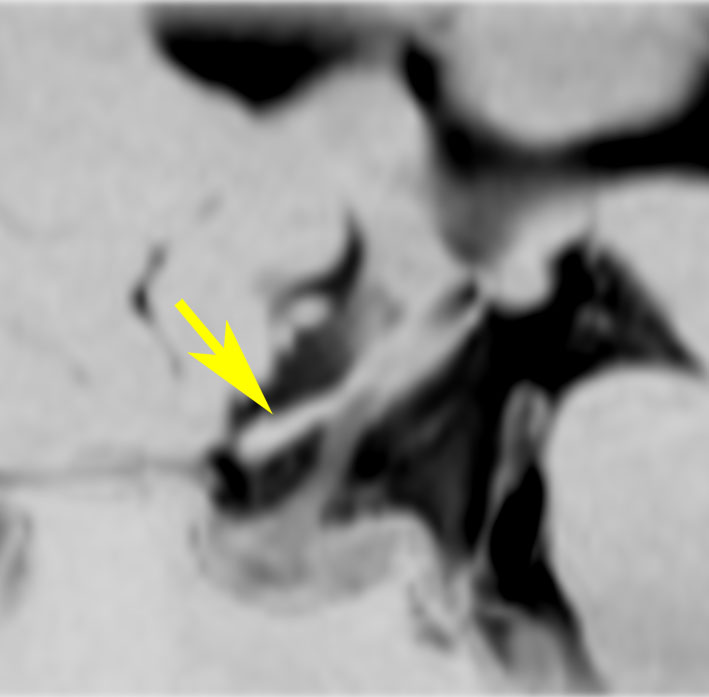

左が16歳,右が23歳の時のMRI画像です。太く見えた視神経が,大きな塊となりました。ガドリニウム増強で,腫瘍の内部が部分的に増強されます。眼球が突出して目を閉じることができず,むき出しになりました。8歳から23歳まで,15年間かかってゆっくり大きくなったし眼窩内神経膠腫です。

CTでは高度の眼球突出があり,腫瘍の辺縁が石灰化していて視神経鞘を含めて極めて硬い線維性腫瘍となっていることがわかります。T2強調画像では高信号で腫瘍が増大傾向を示し,一部が嚢胞性であることがわかります。下のT1増強像では腫瘍の中心部分に増強される増殖部位があることがわかります。